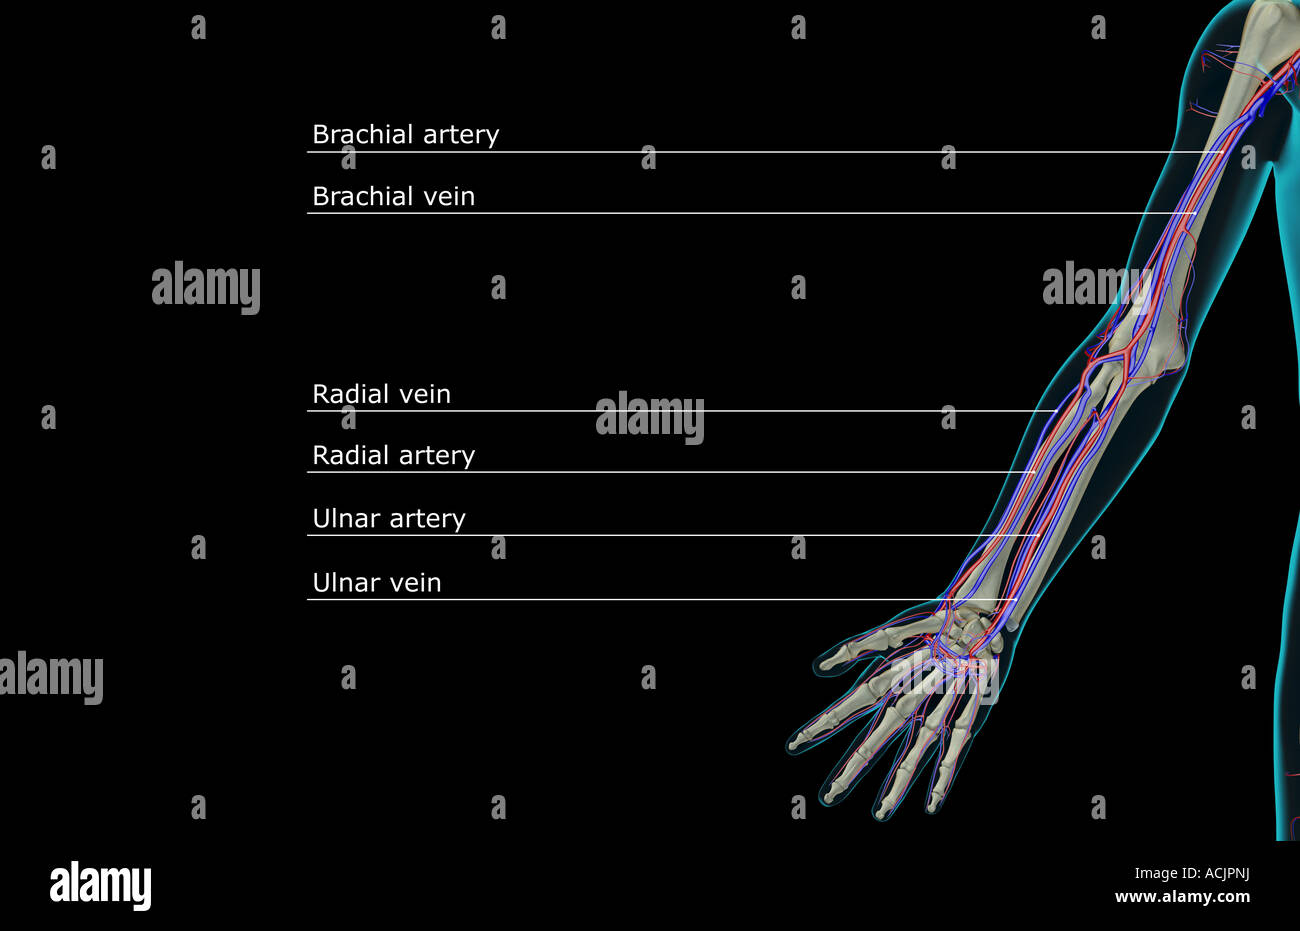

The blood supply of the upper limb Stock Photohttps://www.alamy.com/image-license-details/?v=1https://www.alamy.com/stock-photo-the-blood-supply-of-the-upper-limb-13173892.html

The blood supply of the upper limb Stock Photohttps://www.alamy.com/image-license-details/?v=1https://www.alamy.com/stock-photo-the-blood-supply-of-the-upper-limb-13173892.htmlRFACJXKH–The blood supply of the upper limb